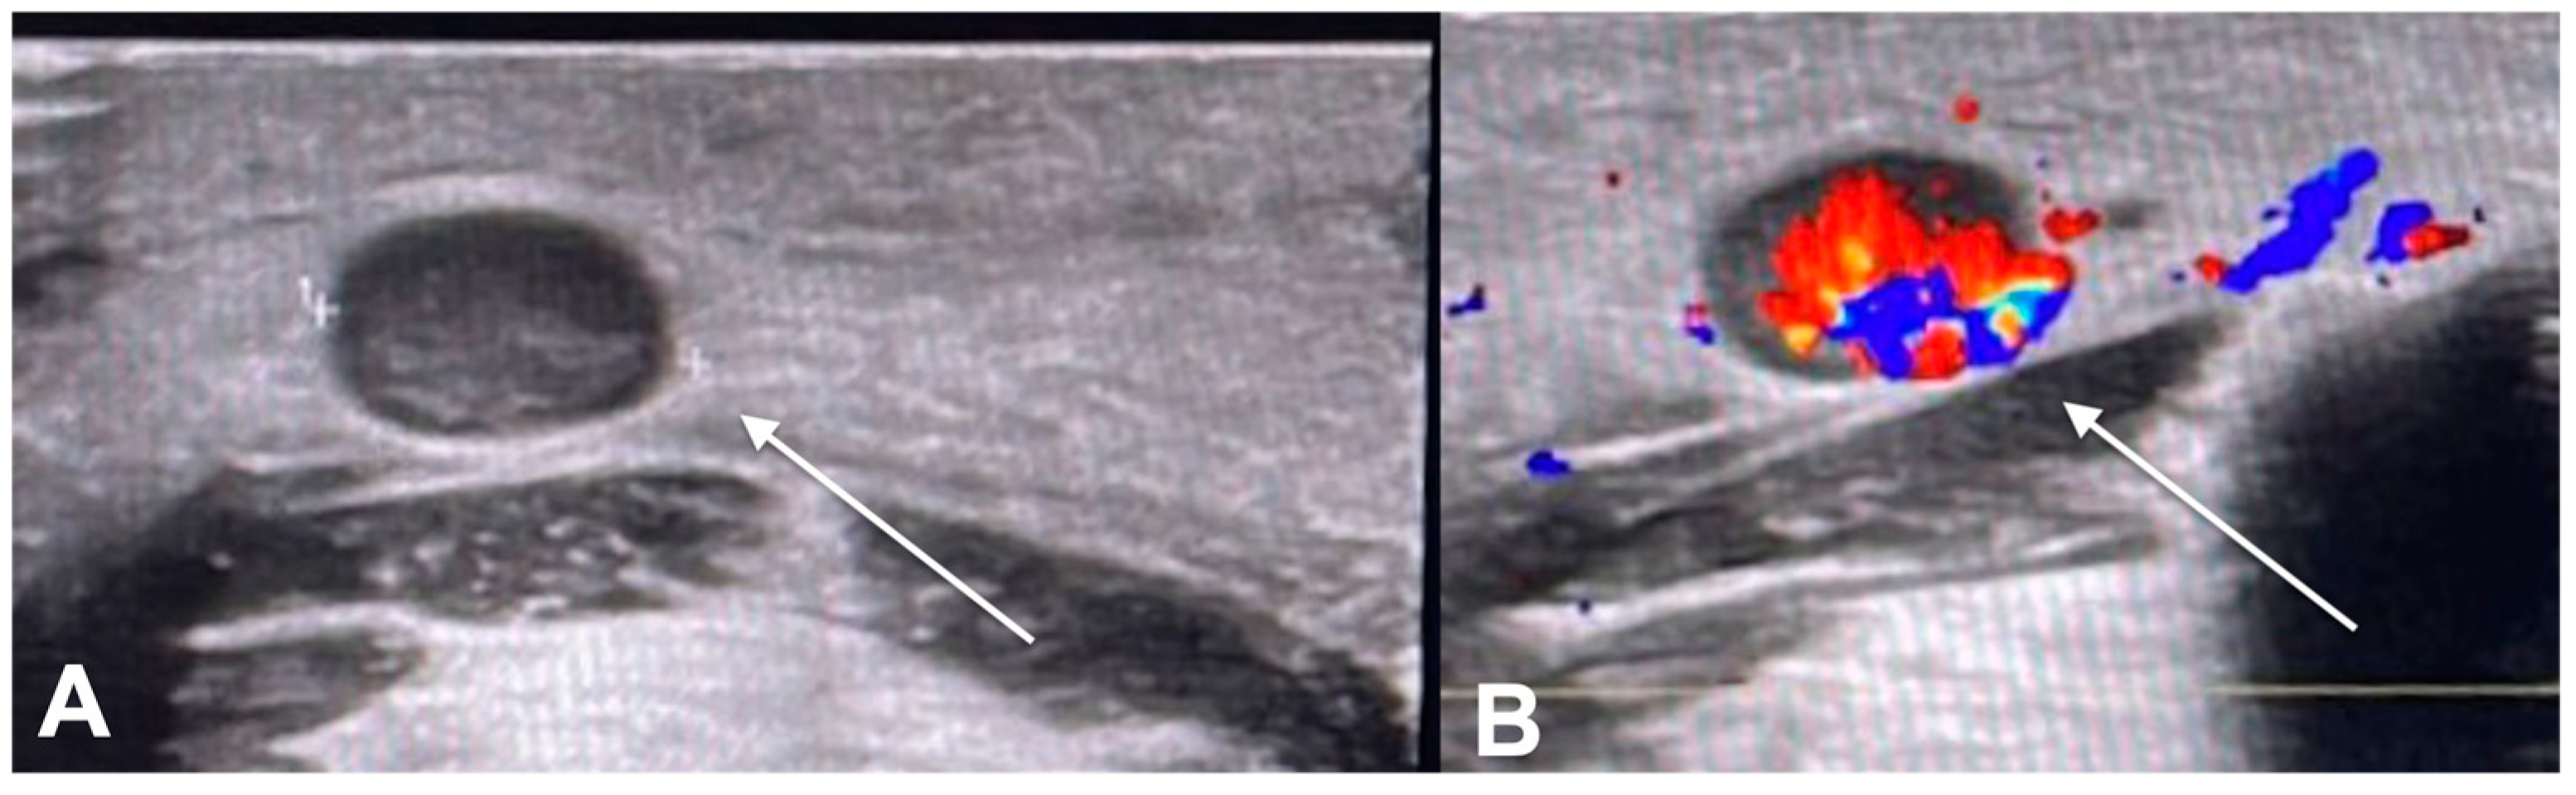

2. Diagnostic Imaging and Non-Melanoma Skin Cancer

3. Diagnostic Tools and Non-Melanoma: Staging and Surveillance